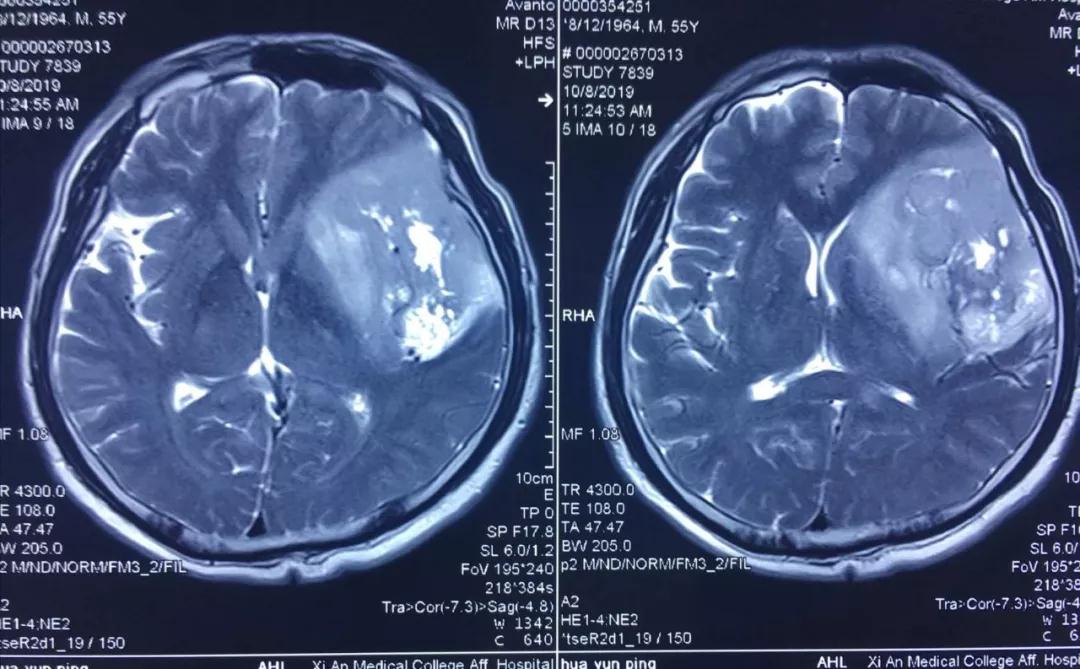

患者李某,今年55歲,因近年出現(xiàn)間歇性面部抽搐,一直未給予重視,近來發(fā)作頻繁,經(jīng)朋友建議在外院行頭顱核磁檢查,發(fā)現(xiàn)顱內(nèi)巨大占位性病變,病變位于左側(cè)額、顳和深部腦島葉,達8.5?5.5?3cm,且侵犯語言功能區(qū),顱內(nèi)占位效應(yīng)明顯,中線偏移1cm,且腫瘤已經(jīng)瀕臨腦疝邊緣,如不及時進行手術(shù)干預(yù),隨時有腦疝可能,危及患者生命。

經(jīng)多方了解后,在朋友的推薦下,患者慕名來到西安國際醫(yī)學(xué)中心找到了腦科醫(yī)院高國棟院長,高院長帶領(lǐng)以賀世明主任為首的神經(jīng)外科團隊,對患者的病情及治療方案等進行討論,憑借多年的臨床經(jīng)驗,結(jié)合患者影像結(jié)果判斷為顱內(nèi)膠質(zhì)瘤,并建議盡快實施手術(shù)切除。